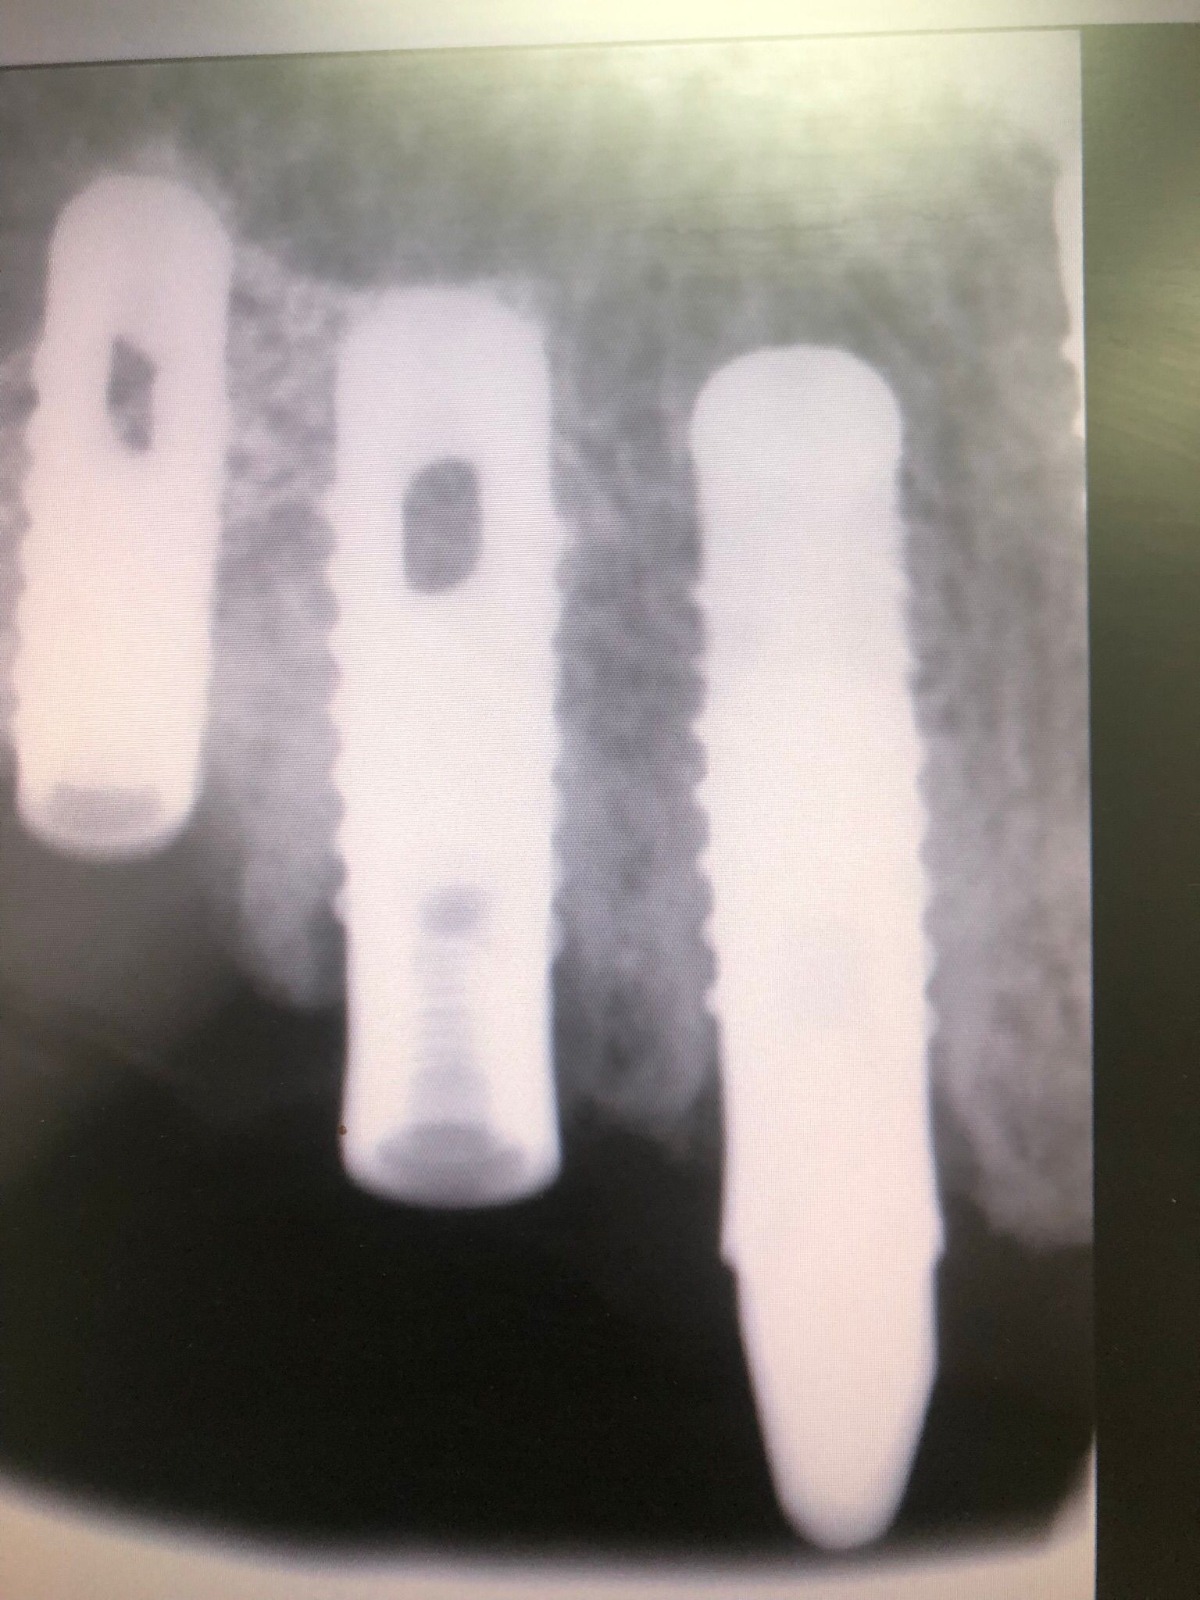

El paciente no presenta incidencias hasta el año 2005, cuando acude a consulta con el segmento distal derecho desprendido y en el que se había producido una fractura de los aditamentos macizos a nivel de la unión del aditamento con implante, de forma que la rosca fracturada del aditamento está encajada dentro de los implantes.

El tratamiento que se intento fue extraer las roscas rotas con ultrasonidos, pero no se pudo, por lo que procedimos a realizar el vaciado de estas roscas rotas y a realizar unas espiras nuevas en estos vaciados con un set de machos roscantes, para después roscar nuevos aditamentos originales de la casa ya fabricados en aleación de titanio (grado V) . Una vez instalados los aditamentos procedimos a su tallado y a realizar la prótesis ceramo–metálica como tenía antiguamente.

Actualmente vuelve el paciente de nuevo con la misma prótesis. Había roto dos de los tres pilares en concreto los más distales. El primero de los dos había roto la rosca del aditamento dentro del implante como ocurre habitualmente. Pero el ultimo pilar había roto directamente la cabeza del implante tal como se ve en la radiografía y lo que quedaba era un cilindro de titanio macizo perfectamente integrado en el maxilar, sin posibilidad de enroscar nada. Le explicamos al paciente que habría que quitar y poner un implante en el mismo acto. El paciente dijo que no, así que decimos que no se haría cirugía. Buscamos solución alternativa: hacemos un un agujero en el centro del macizo cilíndrico del implante roto y pasamos sucesivamente el set de machos roscantes. Utilizamos una fresa cañón de 1 mm que poco a poco se va introduciendo hasta 8mm con un poco de vagación, que hace que sea un poco mas de 1mm de diámetro. Posteriormente pasamos el conjunto de machos roscantes de métrica 2mm para poder usar un aditamento experimental, que era un palo de rosca de diámetro 2 mm unido a un cuerpo metálico en forma de sombrero napoleónico fabricado en cromo/cobalto, prototipos primitivos de la sistemática ASATIM y que tienen la característica de tener gran resistencia a la fractura. Nos llevó un tiempo largo el tallado de dichos aditamentos, tal como se puede observar en las imágenes, y tras cicatrizar la encía se le hizo una prótesis estándar. Esperemos que no lo rompa más veces.